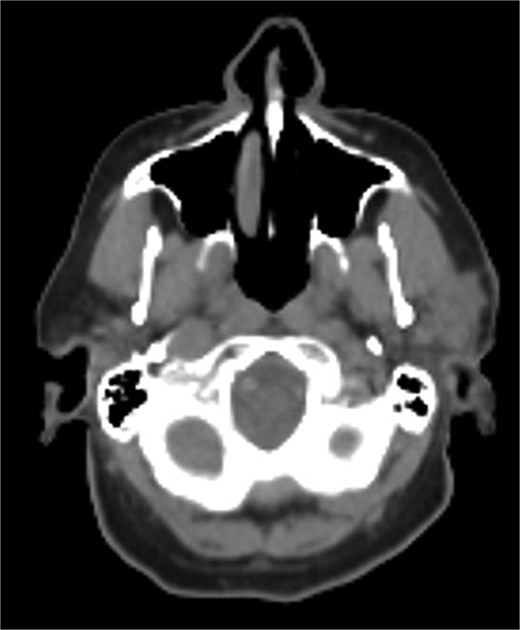

A 75-year-old male presented with several months of left preauricular and upper neck pain. His history included multiple basal and SCCs, Mohs surgery for SCC on the scalp vertex, and a family history of skin cancer. Neck ultrasound revealed anechoic complex areas near the left parotid gland. Imaging identified a hypermetabolic 2.6 × 1.9 × 2.5 cm mass in the superficial parotid and fluorodeoxyglucose (FDG)-avid bilateral lymphadenopathy in level I-III (Fig. 1). FNA confirmed SCC, positive for Keratin, p40, and p63, and negative for Melan A and SOX 10.

Hypermetabolic mass in the superficial anterior left parotid gland measuring 2.8 × 2.5 × 2.6 cm.